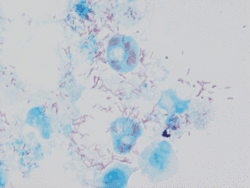

![]() Rickettsia conorii у вигляді червоних стрижнів у культурі клітин Vero (збільшення у 1х103) Rickettsia conorii у вигляді червоних стрижнів у культурі клітин Vero (збільшення у 1х103) | |

Збудником марсельської гарячки є Ricketssia conorii, що має властивості, які притаманні й іншим рикетсіям з роду Rickettsia, родини Rickettsiaceae, ряду Rickettsiales (будова, стійкість, токсигенність, колір та культивування). До цього збудника чутливі в лабораторних умовах морські свинки, білі миші, кролики та мавпи. У штучних умовах R. conorii розмножується у жовтковому мішку курячих ембріонів. На відміну від збудника епідемічного висипного тифу R. conorii при розмножуванні всередині клітини ніколи не заповнює її усю.